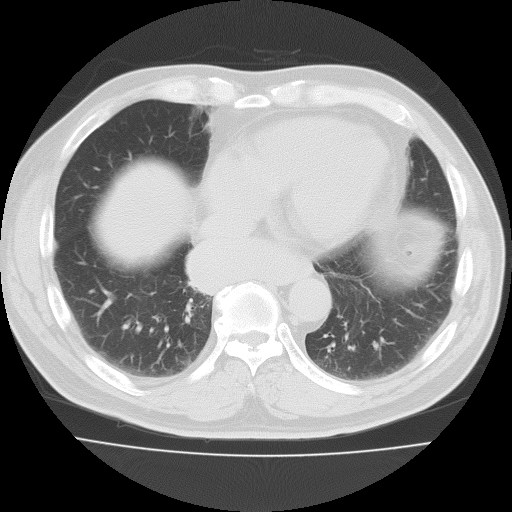

69¼¼ ³²È¯ DM,HTN °ú°Å·Â ÀÖ´ø ȯÀÚ·Î ³»¿ø 10³âÀüºÎÅÍÀÇ right pleural chest pain À» ÁÖ¼Ò·Î ³»¿øÇÑ È¯ÀÚÀÇ CxR ¹× Chest CTÀÔ´Ï´Ù.